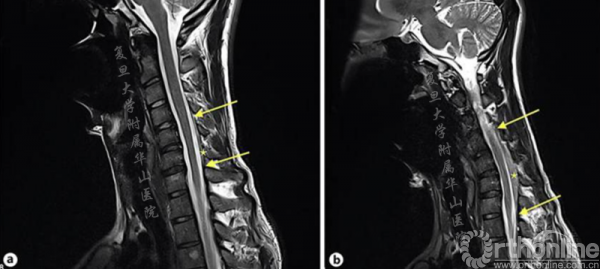

行3T的颈椎磁共振成像(MRI)检查,显示颈部伸直,C5-6节段脊髓萎缩。颈部屈曲时,后方硬膜有前移位,后部硬膜空间扩大,硬膜和椎板间距离增加(从1.4~6.1mm)(图2和3)。

图2.MRI颈椎矢状位T2加权成像,a中立位,显示颈脊髓变直,C5-6水平节段的脊髓变细,可能反映脊髓萎缩;b过曲位,显示后硬膜前移,后硬膜空间扩大,“硬膜椎板间距离”增加,从到1.4~6.1mm(*),脊髓长度增加(←)

中立位MRI往往是正常的,但也可显示脊髓萎缩或颈椎曲度异常(变直或者反曲)。但颈部屈曲时MRI有了改变:后壁向前移位,后硬膜囊与相邻层的附着物消失,椎管内后硬膜外空间有一强化良好的新月形肿块。颈部中立位时消失,有学者认为这是椎体后内静脉丛充血[7]。

Boruah等[16]对45例临床明确的“平山病”患者如此描述:硬膜后方空间的增大和屈曲时颈脊髓变扁是诊断的必要条件。他发现,后硬膜囊最大前移距离在3~9.8mm之间,平均距离为5.99mm。